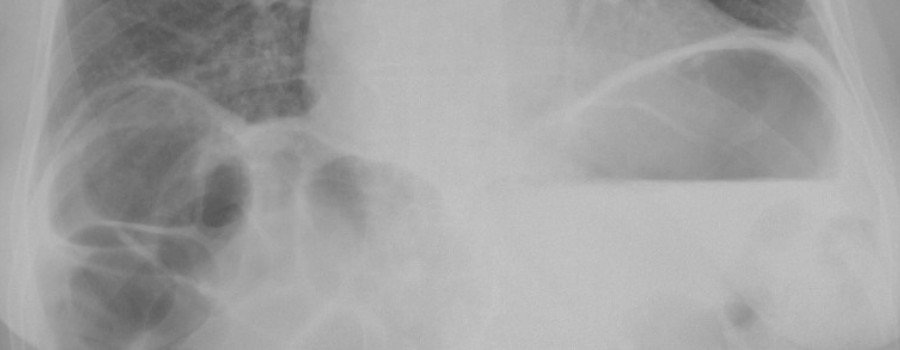

Ganz normales aus einer Notfallambulanz